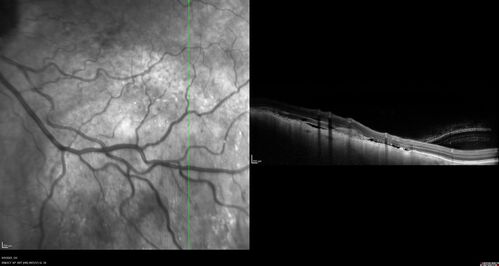

Large chronic choroidal nevus

Autofluorescence image shows guttering at the bottom of the lesion suggesting chronicity. This was documented 23 years prior to these photos